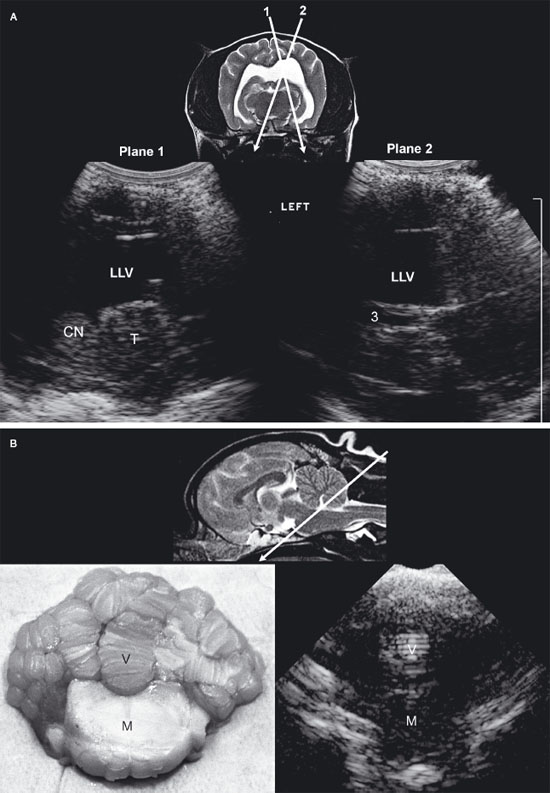

In young puppies, the bregmatic fontanel can be used as an acoustic window to the brain up to approximately 1 month of age (Hudson et al. 1991). In some individuals, particularly in toy-breed dogs, the bregmatic fontanels may persist into adult life. A kitten’s brain can be imaged through the fontanel up to about 5 months of age although accessibility decreases over time (Jäderlund et al. 2003). Unless the fontanel or defect is very large, the tip of the transducer must be held relatively stationary; the transducer can slide only a short distance. The brain is imaged by using a “windshield wiper” technique, with the tip of the probe acting as a pivot point to scan from rostral to caudal and back to obtain transverse images and from side to side to obtain longitudinal images. Because the probe is usually angled to view rostral and caudal structures, most images are made in oblique rather than perpendicular planes (Figure 1.1). Therefore, it should be remembered that, in rostral transverse images, ventral structures seen are actually located rostrally to dorsal structures in the image whereas, in the caudal transverse images, the ventral structures are located caudally to dorsal structures seen in the image.

In absence of a fontanel, a lower-frequency transducer (e.g., 5 MHz) can be used to penetrate the skull, enabling partial visualization of the brain. Penetration of the temporal bone can be used for this purpose in some small dogs in which the brain cannot be otherwise imaged (Figure 1.2A).

Visualization of caudal structures of the brain can be achieved by imaging at the foramen magnum (Figure 1.2B).

Figure 1.1. Normal brain in a dog and ultrasound beams resulting in planes 1 and 2. A: Sagittal magnetic resonance image of the brain of a normal golden retriever illustrating how the ultrasound beam (planes 1 and 2 represented by the arrows) passes through the brain when the beam is placed over the fontanel to obtain transverse sonograms. B: Plane 1 shows the ultrasound beam angled perpendicular to the long axis of the brain to image the rostral horns of the lateral ventricles. C: Plane 2 shows the ultrasound beam angled caudally to image the third ventricle and mesencephalon. D: Transverse magnetic resonance image of the brain of a normal dog showing the axis of an ultrasound beam over the fontanel to obtain midline and parasagittal sonograms (arrows).

Figure 1.2. A: Hydrocephalus. Transverse magnetic resonance image of a dog with hydrocephalus showing the axis of an ultrasound beam to obtain parasagittal images (arrows and corresponding planes 1 and 2). Plane 1 shows the beam angled laterally to obtain a parasagittal image. Plane 2 shows the axis of the beam to image the brain through the temporal bone. 3, third ventricle; CN, caudate nucleus; LLV, left lateral ventricle; and T, thalamus. B: Foramen magnum window. Sagittal magnetic resonance image of a cat showing the axis of the ultrasound beam (arrow) for imaging of the brain through the foramen magnum. The plane of the ultrasound beam passes through the cerebellum and midbrain. A sonogram of a normal cat made through the foramen magnum is on the bottom right. A histological image made in a similar plane is on the bottom left. M, midbrain; and V, vermis.